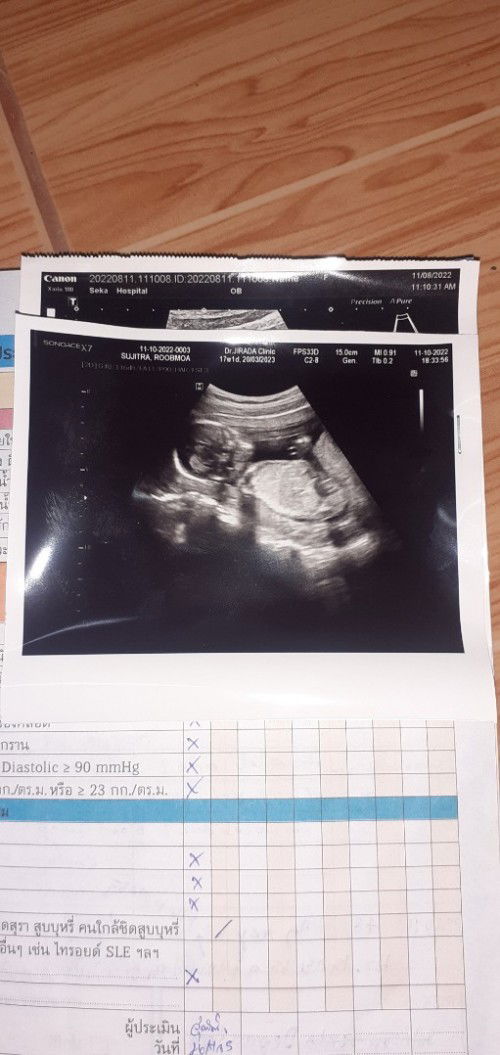

พี่ๆช่วยดูภาพอัลตร้าซาวนี้หน่อยคะเสี่ยงเป็นเด็กดาวน์ซินโดมสูง แม่ไมสบายใจเลย

แม่ที่มีประสบการณ์ช่วยแนะนำด้วยนะ#ขอบคุณล่วงหน้านะคะ

แม่เจาะเลือดตรวจดาวน์ใช่ไหมคะ รึว่าหมอซาวด์ให้ดูแล้วรู้ว่าตรงส่วนคอมือท้องผิดปกติคะ